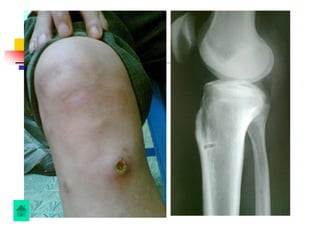

1. Gãy xương hở

*Xuất hiện sau gãy xƣơng hở, thủ thuật trên

xƣơng

*Sƣng, nóng, đỏ, đau, tại vùng gãy xƣơng

*Vết thƣơng tiết dịch đục , có mủ

Xquang: chưa thấy thay đổi cấu trúc trên phim,

đôi khi có phản ứng màng xương

Xquang: Có thể thấy xương chết, xương tù, phản

ứng tạo xương ngoài màng xương